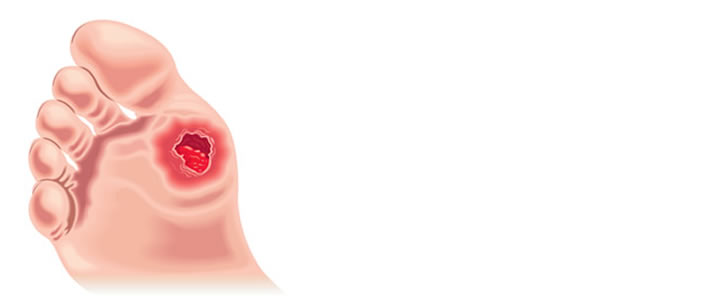

Pé Diabético

O Diabetes Mellitus pode causar uma série de alterações circulatórias, neurológicas, dermatológicas e ortopédicas que propiciam o aparecimento de calos, fissuras, espessamento das unhas, micoses, deformidades ósseas, feridas de difícil cicatrização, infecções e, até mesmo, gangrena em dedos ou nos pés de pacientes com essa doença.

Assim, o tratamento da hiperglicemia e o controle do diabetes é fundamental na prevenção dessas complicações. Cuidados com unhas e pés, uso de sapatos adequados, tratamento de calos e de micoses são fundamentais para a saúde dos pés de pacientes diabéticos. O auxílio do Endocrinologista é fundamental no controle da doença e na prevenção dessas complicações, avaliando periodicamente a sensibilidade e a circulação sanguínea nos pés. O Cirurgião Vascular pode ser acionado no tratamento das complicações circulatórias e infecciosas.